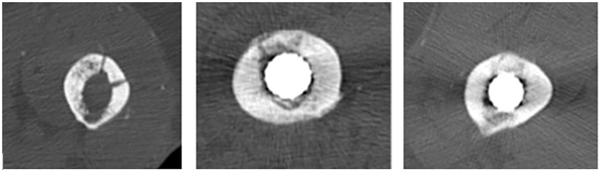

Assessment of imaging

Patients had a limited CT scan of the proximal femur to assess integration of the femoral window from 5 months post-revision surgery. Bony integration of each window was assessed on axial imaging at 10-mm intervals along the length of the window. A scoring system was devised to quantify bony integration of the cortical windows. At each axial interval, complete integration was defined as bony union of both the medial and lateral corticotomy of the window; this was assigned a score of 1. Partial integration was defined as bony union of either the medial or lateral corticotomy; this was assigned a score of 0.5. Non-integration was defined as no bony union of either the medial or lateral corticotomy; this was assigned a score of 0 (Figure 7). The sum of the scores were divided by the number of axial slices assessed, to give an overall integration score ranging from 0 to 1, where 0 represents complete non-integration of the cortical window, and 1 represents complete integration. Assessment of CT imaging was performed by 2 authors plus a consultant radiologist from our institution. The same axial CT images were assessed by each author on 2 occasions, separated by a period of at least 2 weeks.

Figure 7

Axial CT slices demonstrating non-integration Score 0 (left), partial integration, score 0.5 (centre), and complete integration score 1 (right) of the femoral cortical window.

Radiographs confirmed 2 cases of femoral stem subsidence of 1 cm. Both stems stabilised subsequently. CT scans were performed between 5 months and 9 years postoperatively (mean 30 months) (Table 1). The mean rectangular-shaped window size was 8 × 1.5 cm, with width variation of 1–2 cm. Average overall integration score was 0.84 (range scores 0.44–1). 3 patients demonstrated complete union of the cortical window. Using interclass correlation coefficient, inter-observer agreement was 0.86, and mean intra-observer agreement was 0.88 (0.79, 0.92, 0.92) for the first 16 cases. Values >0.8 are considered to show very good agreement, and >0.9 show excellent agreement.

Average overall integration score for aseptic cases was 0.85 (range 0.63 to 1, n = 16), and for septic cases was 0.77 (range 0.44–0.98, n = 6). Levene’s test for equality of variances analysis showed no statistically significant difference between integration scores (p = 0.324). Given the integration scores shown in Table 1 we suggest that most integration occurs within 6 months of surgery.